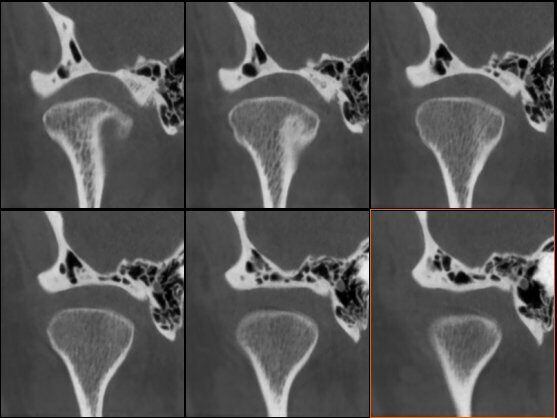

ATM Bocca Chiusa